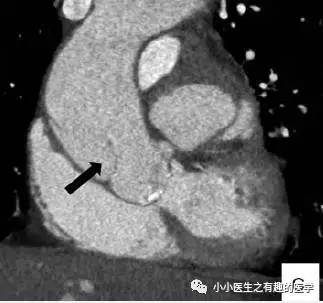

文献3:足球王国巴西报道的一例。

这是什么?

病理:Intimal sarcoma of the pulmonary artery:肺动脉内膜肉瘤。

仔细看看:

CT示肺动脉内肿块,肿块侵犯纵膈,血栓不会跑到纵膈。